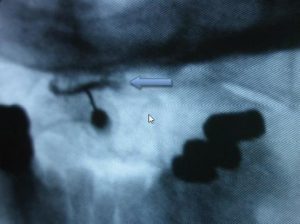

Rutura Interna do Disco L4 / L5 às 4 horas com distribuição circunferencial do contraste radiológico (em branco na TC)